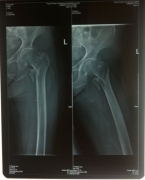

7月9日,莆田盛興醫(yī)院為一名89歲的女性髖部骨折患者順利實(shí)施了手術(shù)。   數(shù)日前,東……

近日,平海鎮(zhèn)90歲高齡的周阿婆即將出院。她感慨地對筆者說:“真沒想到我還能下床走路……